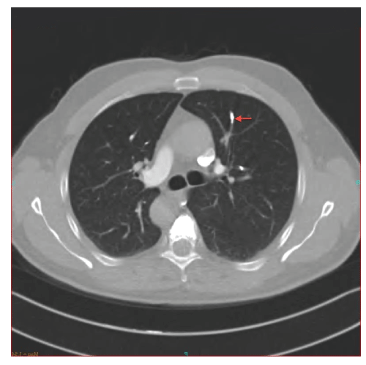

48岁男性,有慢性阻塞性肺疾病病史,诊断为复发性葡萄膜炎,但没有结节病或结核病的证据。他接受了脉冲类固醇和口服类固醇作为维持治疗葡萄膜炎。他还有30年的吸烟史。骨质疏松症继发自发性椎体压缩性骨折。每11个椎体均行经皮椎体成形术。术后第一天患者突然出现呼吸急促、胸痛和心动过速。血压正常,心率116 /min。肺听诊叩诊清晰,心脏及其他查体正常。血液化学分析及pH: 7.46, pCO无明显变化2: 38mmhg, pO2: 58mmhg, HCO3.: 28, SaO2: 91动脉血气分析。胸部计算机断层CT血管造影显示右上、下叶半奇静脉内因辐射不透明而出现致密物质(图1-3)。行超声心动图及下肢多普勒超声检查,未见病理改变。这些结果与水泥PMMA肺栓塞、低分子肝素低分子肝素抗凝和氧疗相一致。一周后,低氧血症得到缓解,患者接受低分子肝素治疗出院回家。对照组CT血管造影显示6个月时PMMA栓塞无变化,并行通气灌注闪烁(VQ)检查。VQ扫描也显示右上叶前部和左上叶尖后低灌注失配区,但患者治疗后无症状(图4、5)。

图4:低分子肝素治疗后胸部CT检查

图5:低分子肝素治疗后胸部CT检查